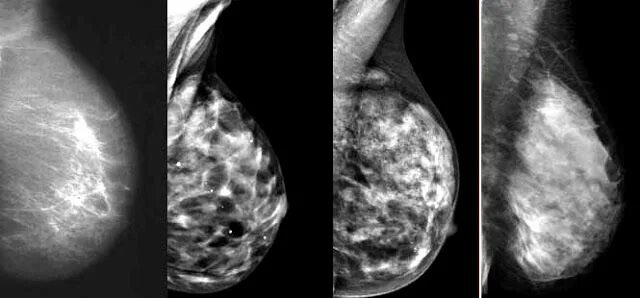

Тип молочных желез acr 2